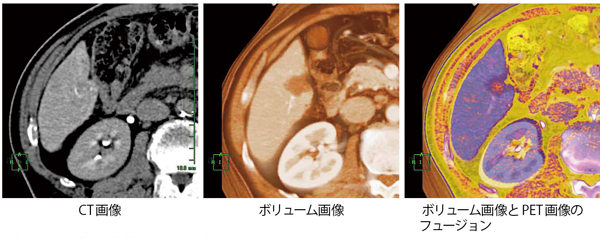

PETやSPECT画像とCT画像との重ね合わせや,MR画像でシーケンスが異なる画像(T2強調像とディフュージョン画像など)を作成することで,位置情報と血流動態情報を1画像として観察できる(図4)。FOVやマトリックスサイズも自動で合わせることができる。RFA(Radiofrequency Ablation Therapy)治療前後などの評価にも有用で,フュージョンイメージは,RFAの治療範囲が安全マージンを持って焼灼されているかを把握するのに有用である(図5)。また,PET画像を用いた場合にはSUV計測も可能である。

図4 造影CTとFDG-PETのフュージョン

図5 RFA治療前後のフュージョン